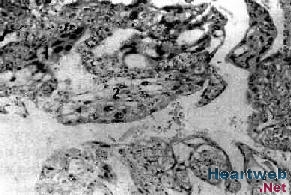

6、宮切除後,病理檢查可確診。病理特點為葡萄胎組織侵入肌層,滋養細胞增生活躍,組織壞死、出血,可見到絨毛結構。

4.組織學診斷單憑刮宮標本不能作為侵蝕性葡萄胎的診斷依據,但在侵入子宮肌層或子宮外轉移的切片中,見到絨毛結構或絨毛退變痕跡,即可診斷為侵蝕性葡萄胎。若原發灶與轉移灶診斷不一致,只要任一標本中有絨毛結構,即應診斷為侵蝕性葡萄胎。